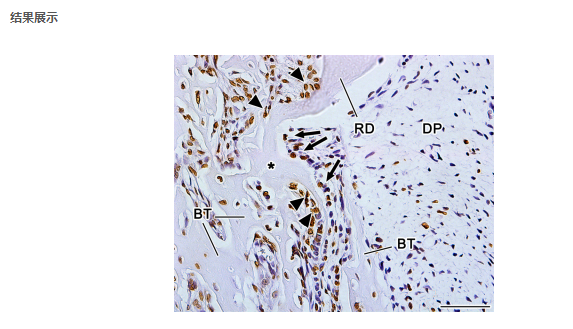

2.交付标准:蜡块、切片、染色图片.实验报告(实验步骤、试剂、耗材等)